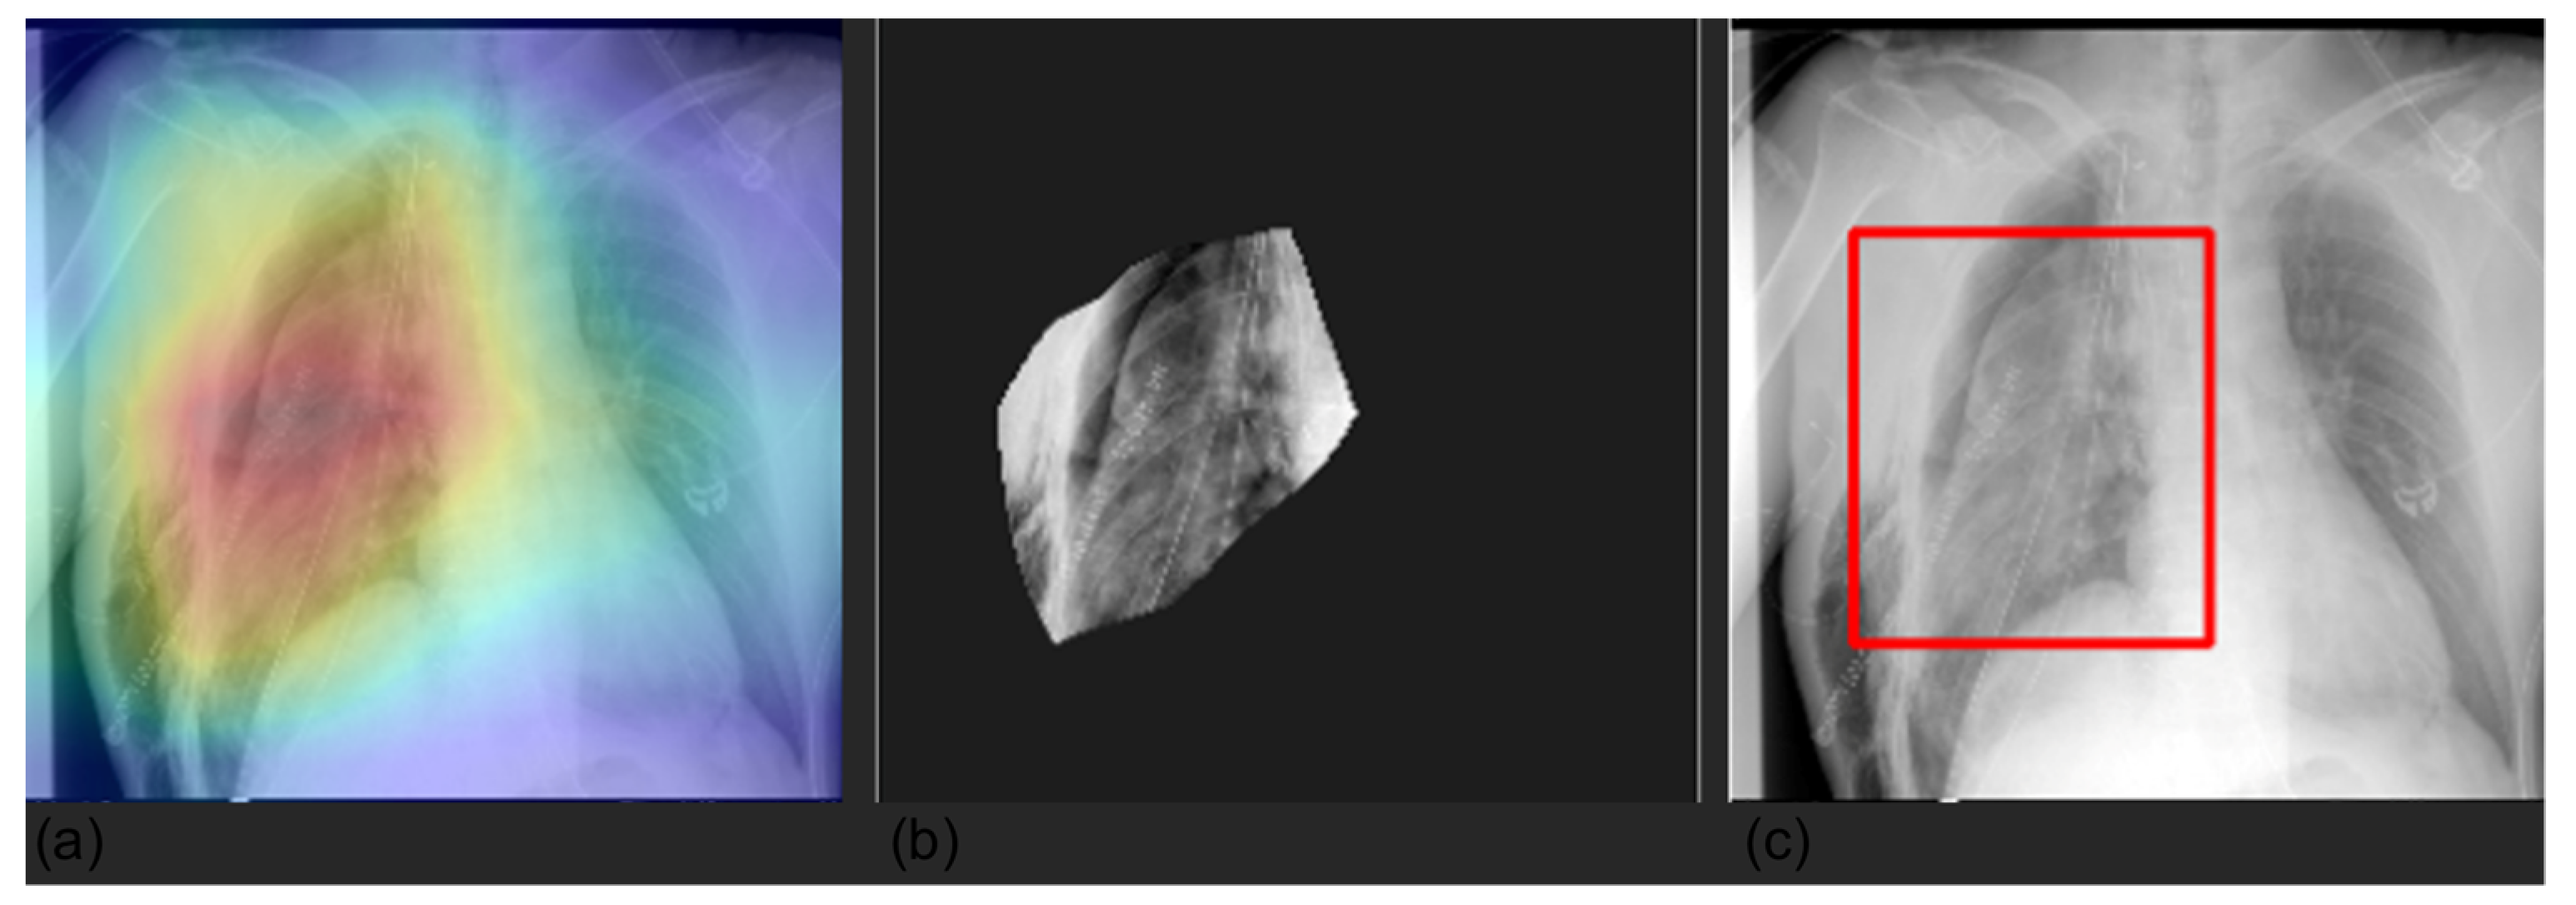

3.4. Grad-CAM